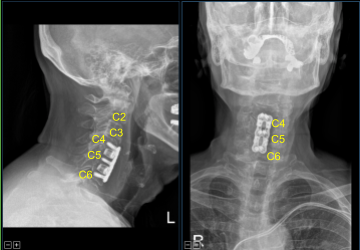

Trials were used to select a 7 mm lordotic titanium interbody spacer which was filled with morselized autograft and allograft and gently tamped into C4-5 and C5-6 interspaces with a mallet into the correct position. Caspar pins were removed. The bony defect was waxed.

There was no significant change, so the interbody spacer was replaced. Anterior osteophytes were flushed with an electric high-speed drill. Hemostasis was obtained with bone wax. Titanium lordotic plate was placed from C4 to C6 and secured with a pin.

Fluoroscopy showed correct sizing and positioning, so it was secured with six 14 mm titanium screws decorticating with a handheld 12 mm electric drill. AP and lateral fluoroscopy showed good positioning. All the screws were final tightened using an integrated device in the plate.

The patient initially followed up two weeks after the surgery and then continued following up in our office periodically. In their visit the patient stated that they had experienced improvements with their radiculopathy.